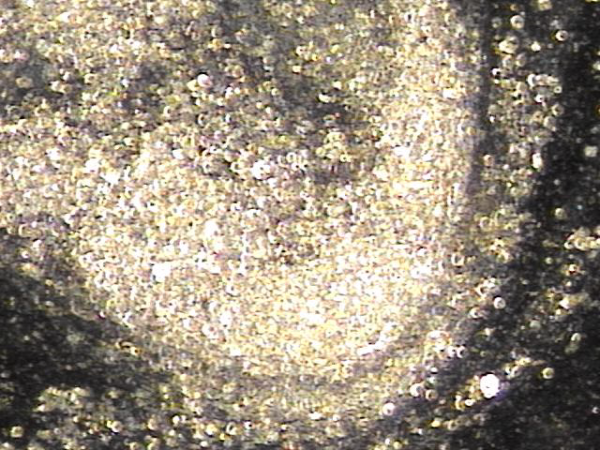

내원 첫날 전립선의 표적 치료후 치료된 정낭의 혈정액과 정자들과 염증들의 현미경학적 자료입니다.

This is a microscopic image taken after your first targeted prostate treatment, showing improvement in the seminal vesicle.

The blood-tinged fluid (hematospermia), sperm, and inflammatory cells have been successfully treated.